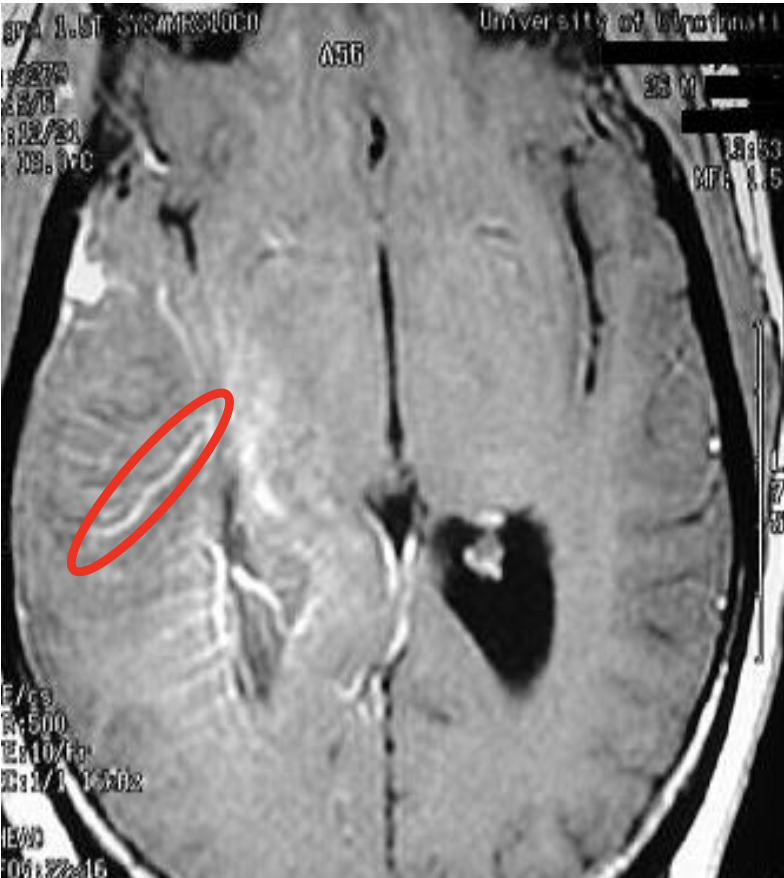

Chronic cortical ischemic stroke

Aftermonths,allthat remains is a cystic cavity surrounded by gliotic tissue with glial strands (circle)

-There is compensatory (ex- vacuo) ventricular enlargement (open arrow)

Wallerian degeneration of the cerebral peduncle and corticospinal tract in the pons. (arrows)